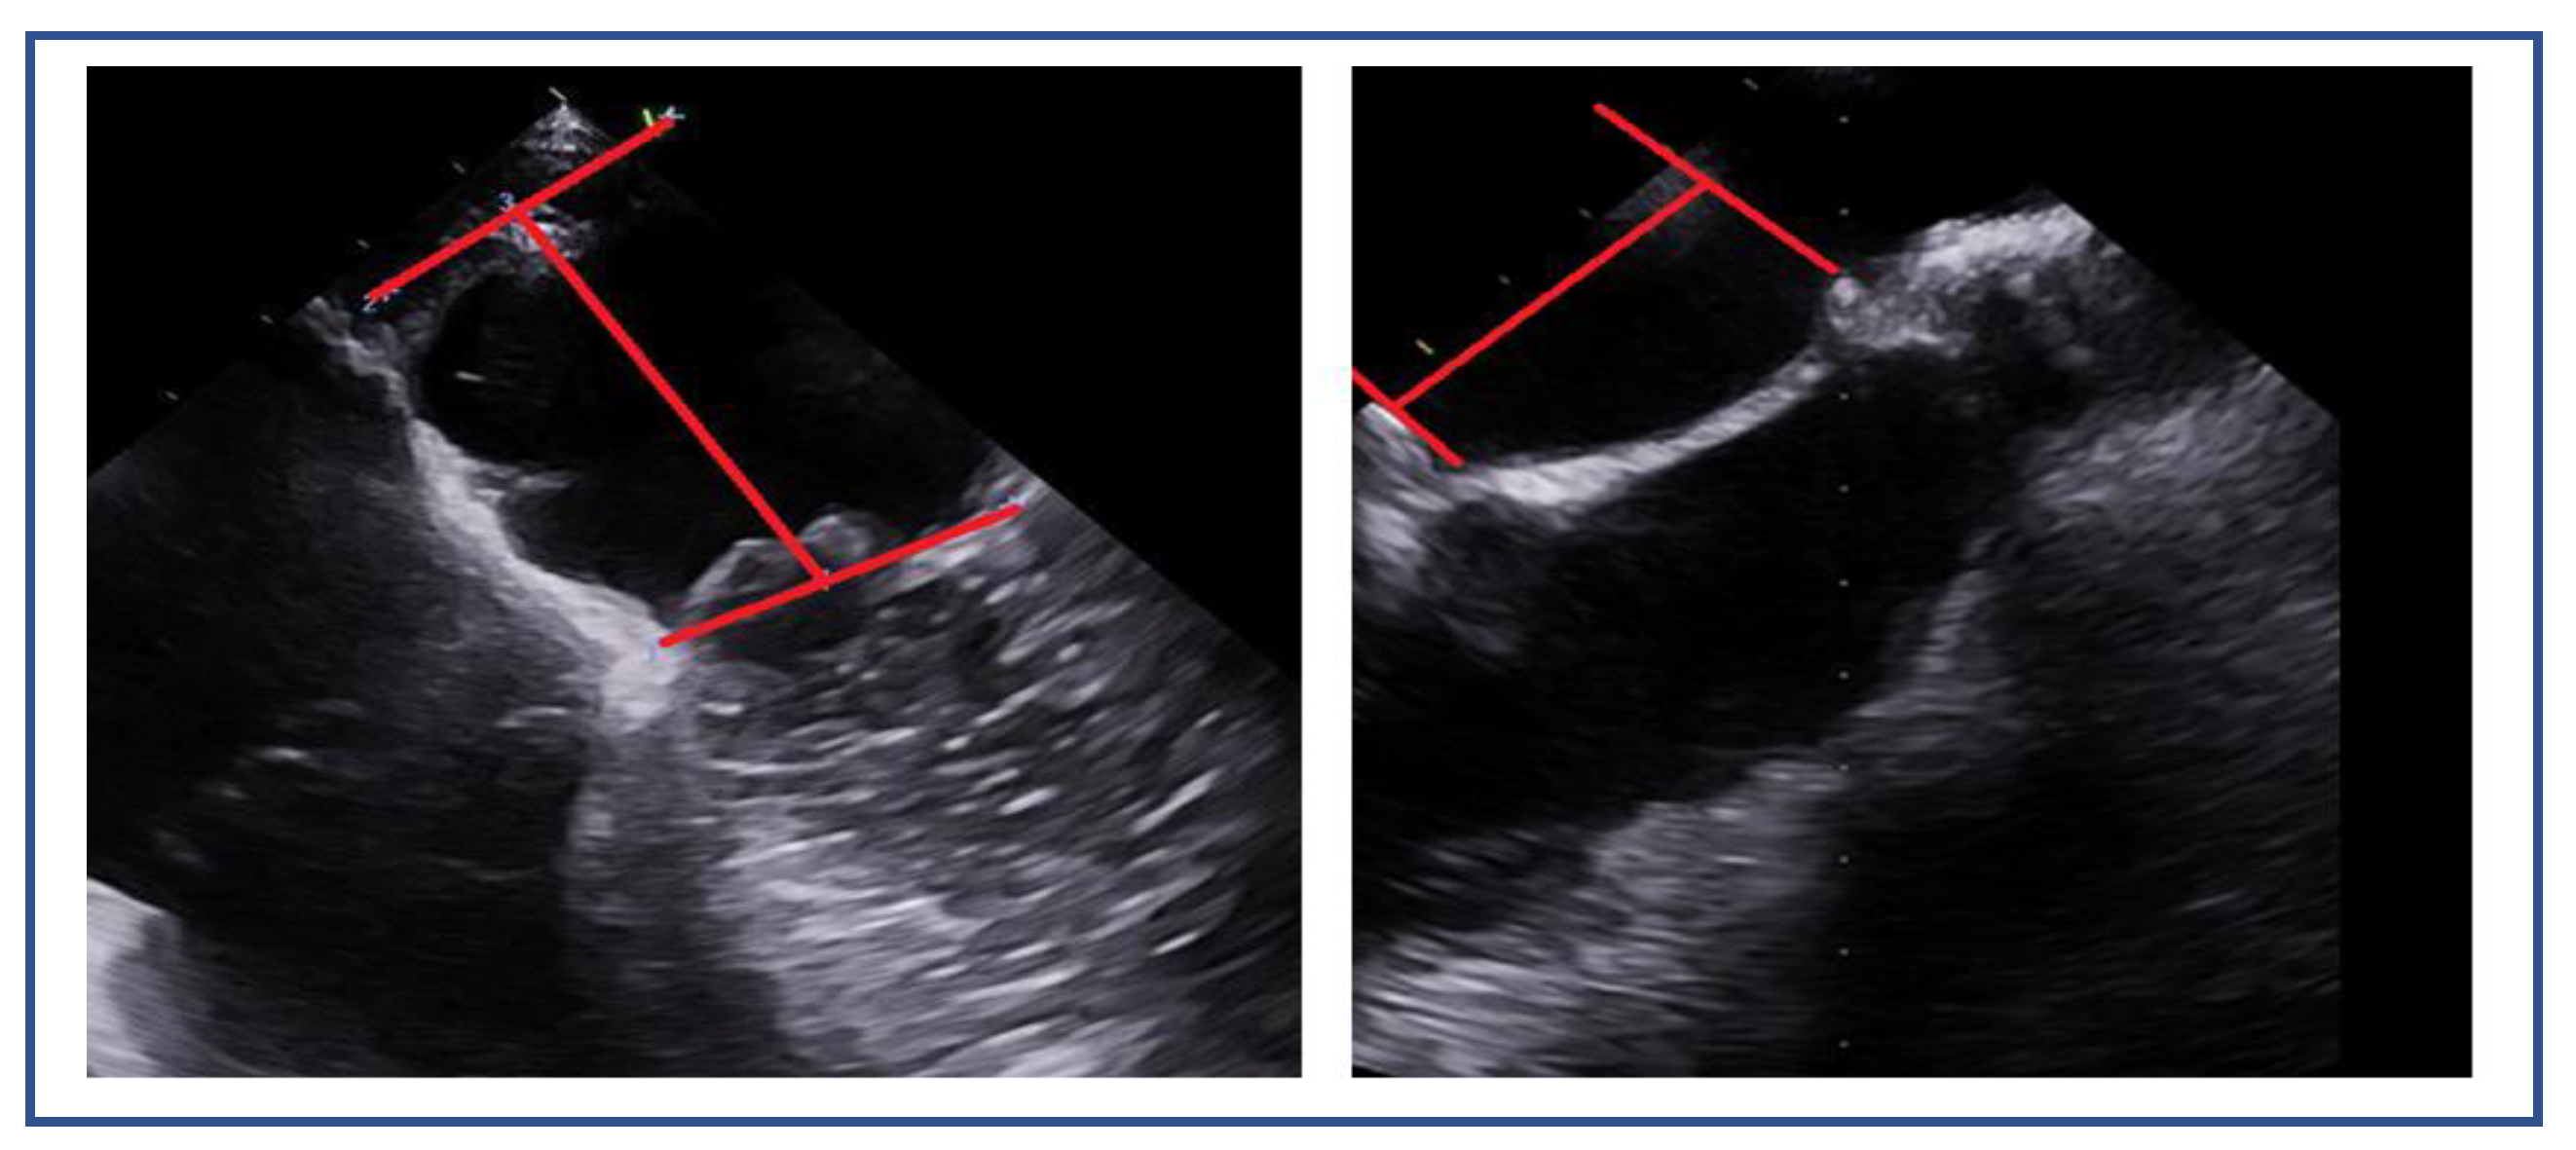

7.4. Flail Gap and Width (PMR)

7.5. Tenting Height and Coaptation Length (SMR)